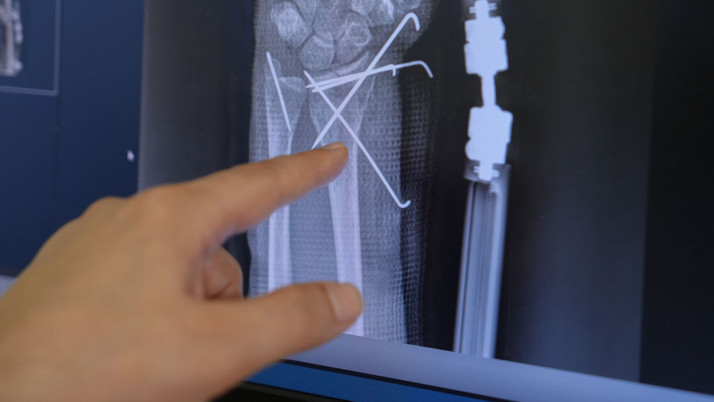

Ameliyatın çok başarılı geçtiğini ve hastanın birkaç hafta içerisinde toparlanacağını belirten Medipol Mega Üniversite Hastanesi’nden El Cerrahisi Uzmanı Dr. Öğr. Üyesi Kadir Uzel, “Hastamız düşme sonrası kalça ve el bileğinde eklem içi parçalı kırığı nedeniyle hastanemize başvurmuştu. Prof. Dr. İbrahim Azboy hocamız kalça kırığı için total kalça protezi uygulaması yaptıktan sonra, hastayı el cerrahisi ekibi olarak devraldık. Sonra el bileğindeki eklem içi parçalı kırığını ameliyat ettik. Ameliyat sırasında ve sonrası yaptığımız görüntüleme yöntemlerinde kırığın gayet düzgün bir şekilde tedavi edildiğini gördük. Hastamızın ameliyat sonrası parmak hareketlerine hemen başladık. Şu an gayet iyi. Ağrısı yok. 6 hafta sonra kırık tespiti için kullanılan k telleri ve eksternal fiksatör sistemi çıkarıldıktan sonra hastanın fizik tedavi süreci başlanacak. Fizik tedavi süreci sonrasında da hastamız el bileğini ve elini, sağlıklı eli gibi kullanmaya başlayacak.” dedi.